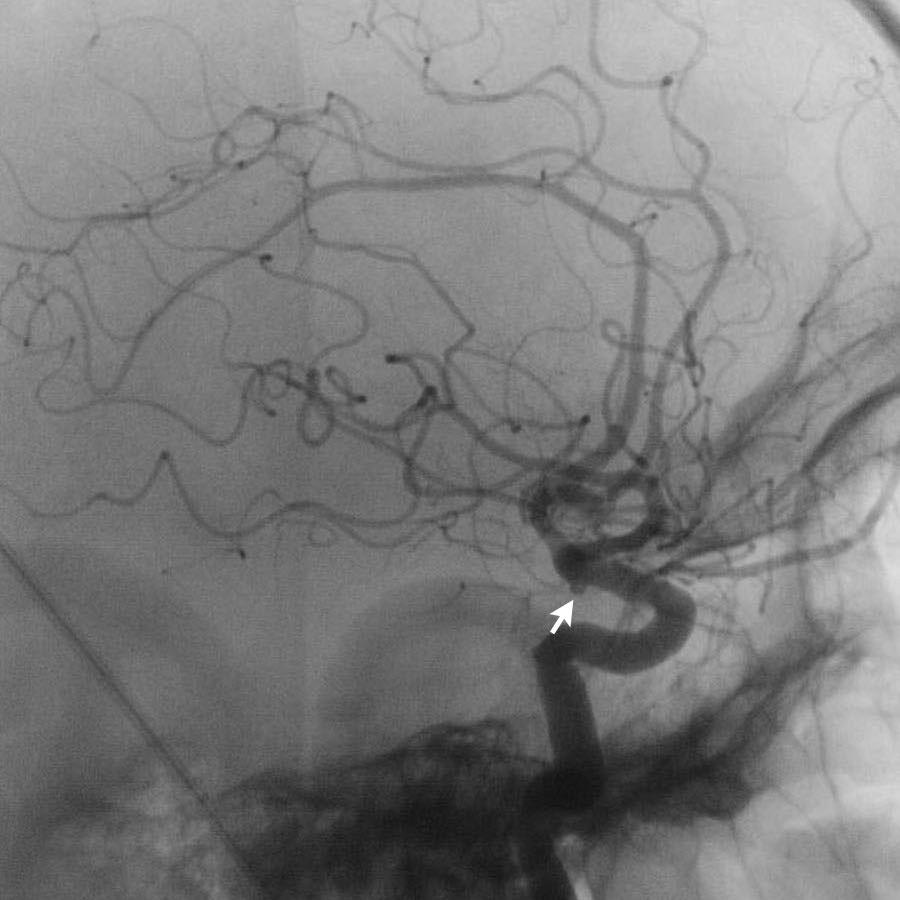

Bệnh nhân này có túi phình tại nguyên ủy của động mạch tiểu não sau dưới trái (PICA).

Cũng cần lưu ý tình trạng não úng thủy.

Bệnh nhân này được thực hiện chụp mạch số hóa xóa nền (DSA) và sau đó được nút coil.

DSA cho thấy một túi phình hình túi của PICA trái, đường kính tối đa 6 mm với cổ ngắn và hẹp.

Phình động mạch hình túi là loại phình động mạch phổ biến nhất. Chúng có hình tròn hoặc thùy và xuất hiện tại các vị trí phân nhánh của đa giác Willis.

Chúng có thể xuất hiện nhiều ổ trong 20% trường hợp. Trong 5% trường hợp, kích thước vượt quá 2,5 cm và được gọi là “phình động mạch khổng lồ”.

Các loại phình động mạch khác bao gồm phình hình thoi (giãn khu trú cực độ trong bệnh xơ vữa động mạch) và phình động mạch do nấm (mycotic). Loại sau biểu hiện là các ổ máu tụ trong nhu mô não ở vị trí ngoại vi, kèm theo phù chất trắng xung quanh vùng xuất huyết. Chúng do thuyên tắc nhiễm khuẩn ở bệnh nhân có nhiễm khuẩn huyết đã biết.

Vị trí của túi phình động mạch có thể được dự đoán dựa trên vị trí của xuất huyết.

Hình ảnh cho thấy xuất huyết dưới nhện từ túi phình động mạch não giữa trái.

Tiếp tục với DSA…

DSA xác nhận PICA phải kèm túi phình (mũi tên) dẫn đến nidus (vòng tròn).

Nidus được dẫn lưu bởi cả tĩnh mạch nông và tĩnh mạch sâu (không hiển thị riêng biệt ở đây).

Các phát hiện phù hợp với AVM – Spetzler-Martin độ 2:

- Nidus nhỏ (<3 cm): 1 điểm

- Vị trí vùng não không chức năng quan trọng: 0 điểm

- Kiểu dẫn lưu tĩnh mạch bao gồm cả thành phần nông và sâu: 1 điểm

Túi phình hình túi xuất phát từ PICA được giải thích là túi phình liên quan đến dòng chảy.

Do sự thay đổi huyết động học gây ra bởi AVM, thành mạch có thể bị suy yếu và hình thành túi phình.

Các hình ảnh cho thấy DSA trước và sau khi đặt coil túi phình.

PICA, nidus và các tĩnh mạch dẫn lưu bất thường (cùng tạo thành AVM) vẫn còn ngấm thuốc tương phản.

Quyết định không điều trị trực tiếp AVM mà lựa chọn theo dõi và có thể can thiệp phẫu thuật trong tương lai.